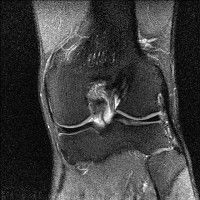

무릎 mri 간단히 봐주실 수 있으시나요 ㅠㅠ

안녕하세요 8년전 십자인대 수술하고 최근 무리한 운동에 무릎 불편감이 생겨서

mri 찍었습니다.

진단결과는 첫 찍은 병원에서 활액막염 이라는 진단을 받았습니다. 혹시 봐주실 수 있으실까요?

올라온 MRI가 단편적이라서 정확한 진단에 어려움이 있지만 십자인대에는 큰 이상이 있지는 않은것 같으며, 무릎관절내 물이 있는 것으로 보아 활액막염의 진단이 맞을 것 같습니다.

하지만 단편적인 영상이기 때문에 촬영병원에서 정확한 판독지 등을 받으시는 것이 좋겠습니다.